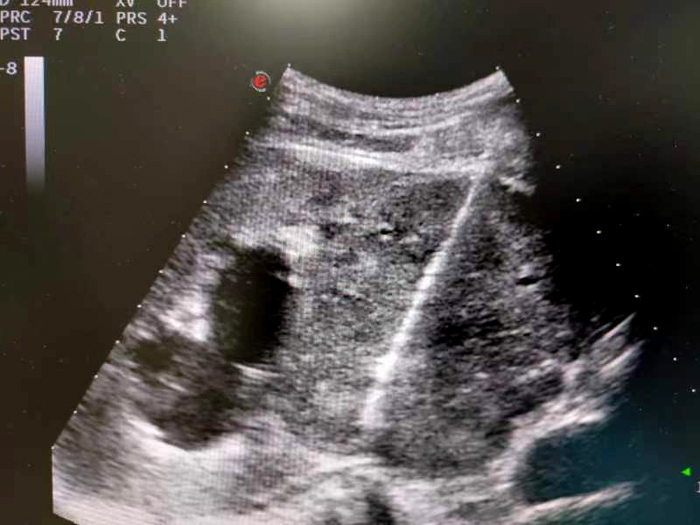

腎臟腫物穿刺活檢